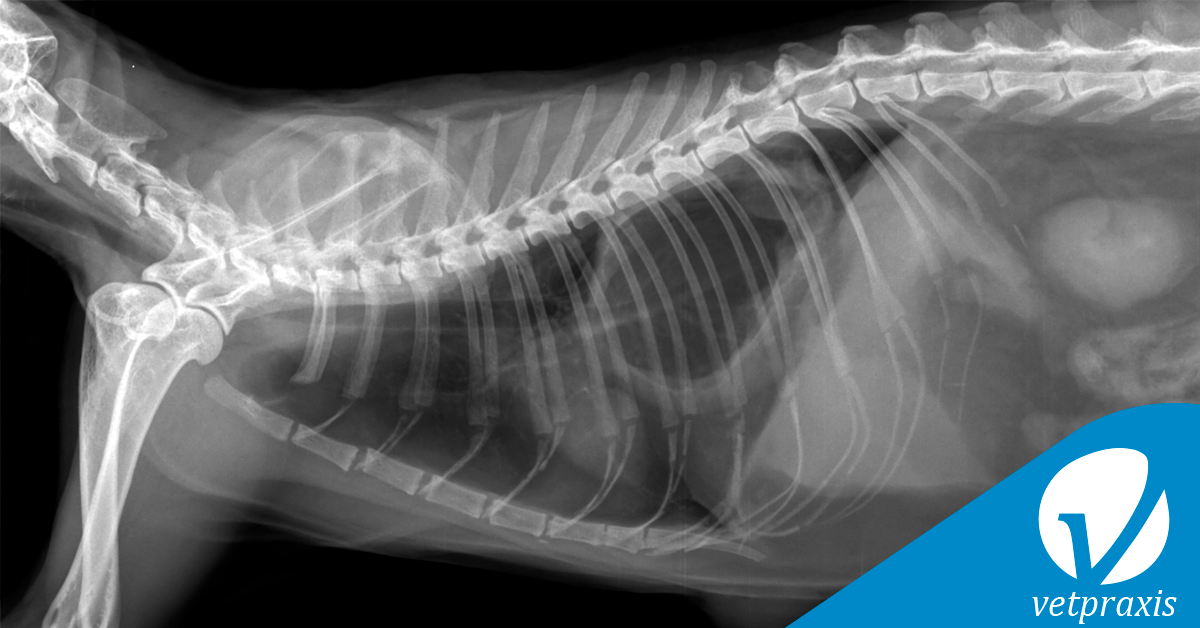

Paciente felino de 12 años con distress respiratorio severo peragudo, cianosis leve. Se presenta un abultamiento de pared corporal ventral a la altura de VIII esternebra.

Se adjuntan proyecciones simples L-L y V-D (de discreta oblicuidad) de tórax.

Indique el radiodiagnóstico considerando claves para justificarlo.

a) Rotura diafragmática traumática

b) Intususcepción gastroesofágica